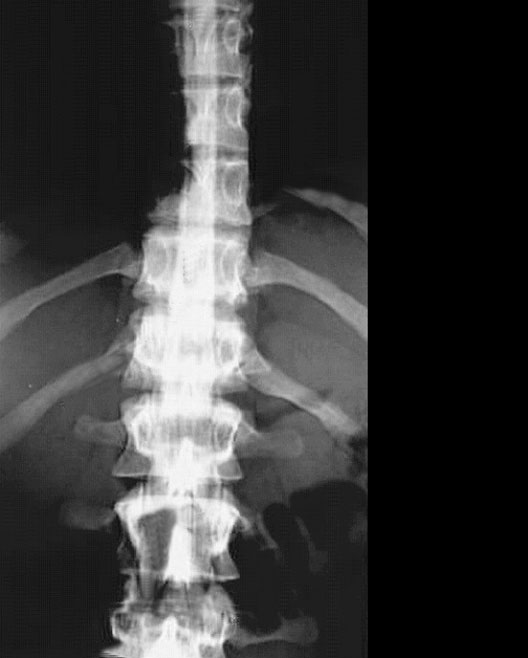

Lumbar Myelogram

1. Spinal cord

2. Contrast material in subarachnoid space

3. 12th Rib

4. Nerve rootlets of cauda equina

5. Intervertebral disc